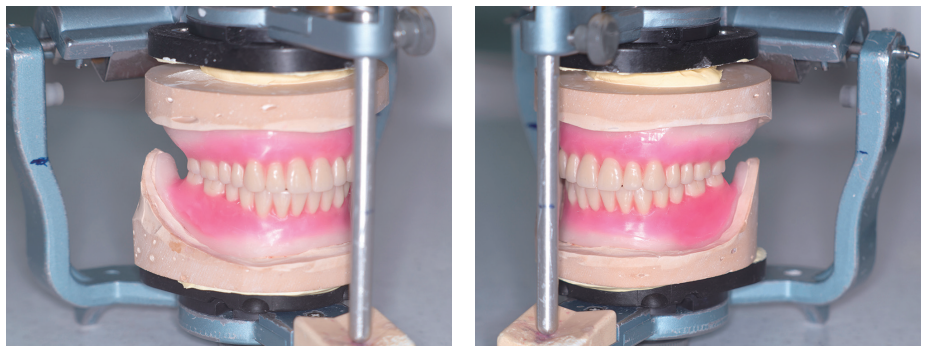

먼저 occlusal plane plate를 이용하여 상·하악 wax rim 교합평면을 조정한다.

Willis’ gauge를 이용하여 대략적인 VD를 찾는다. VD가 결정되면 Gnathometer M을 부착할 공간을 4mm 정도 삭제한다.

4) Gnathometer M 부착과 내면조정

Gnatometer M 수평 상태를 구강 내에서 확인하였다.

Fit checker를 이용하여 base plate 내면검사를 하고 심한 접촉 부위를 삭제하였다.

5) 상·하악 active functional impression

Gnathometer M이 부착된 tray를 이용해서 상악부터 실리콘 인상재를 이용하여 기능인상을 채득하였다.

이어서 하악도 기능인상을 채득하였다.

6) VD, CR 채득

Gothic arch tracing이 어느 정도는 형성되었다.

Tapping point와 apex 거리는 3mm 정도 떨어져 있지만 tapping point를 CR로 선택하였다. 이것은 하악이 전방으로 많이 돌출되어 있는 상태를 의미한다.